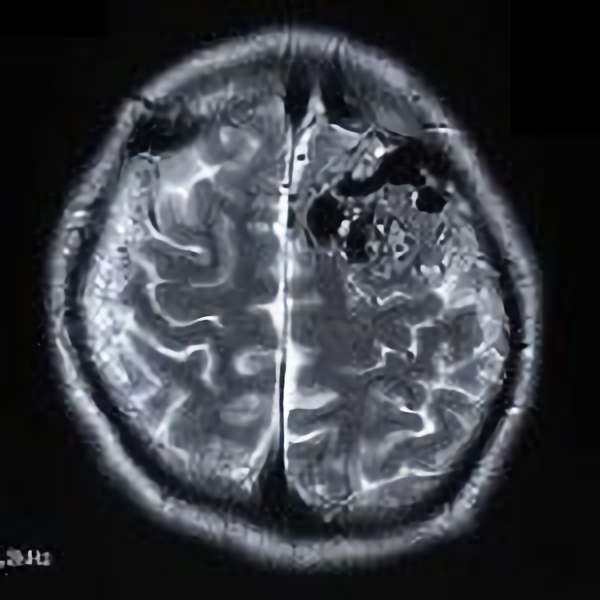

脳血管撮影

手術前

手術後